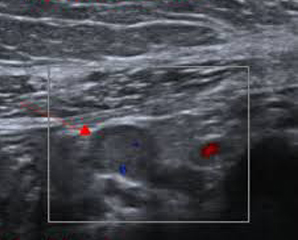

Aspect echographique

d'une diverticule Meckel . Image hypo-echogene de la

paroi oedeme infecte et iso -echogene du contenue .

Echographie en coupe longitudinale . |